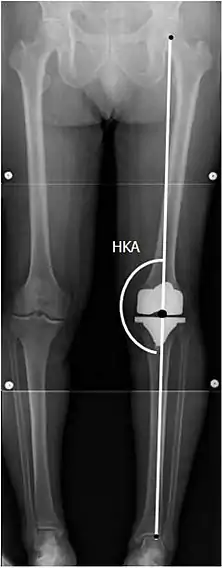

![]() |

Angles commonly measured before knee replacement surgery: |

To indicate knee replacement in case of osteoarthritis, its radiographic classification and severity of symptoms should both be substantial. Such radiography should consist of weightbearing X-rays of both knees- AP, Lateral, and 30 degrees of flexion. AP and lateral views may not show joint space narrowing, but the 30 degree flexion view is most sensitive for narrowing. Full length projections are also used in order to adjust the prosthesis to provide a neutral angle for the distal lower extremity. Two angles used for this purpose are:

- Hip-knee-shaft angle (HKS),[8] an angle formed between a line through the longitudinal axis of the femoral shaft and its mechanical axis, which is a line from the center of the femoral head to the intercondylar notch of the distal femur.[10]

- Hip-knee-ankle angle (HKA),[9] which is an angle between the femoral mechanical axis and the center of the ankle joint.[10] It is normally between 1.0° and 1.5° of varus in adults.[11]